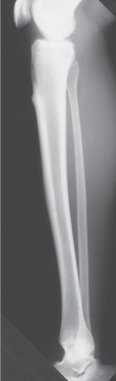

What projection of the leg is this

lateral leg projection

What type of lateral is a lateral leg projection

mediolateral

Patient position for a lateral (mediolateral) leg projection is

supine, rotated towards affected side

In a lateral leg projection, femoral condyles are ____ and ___ to IR

superimposed, perpendicular

For a lateral leg projection, the CR enters at

midpoint of leg

Distal fibula superimposed by posterior half of

the tibia

• Slight overlap between tibia and fibular head

• Separation of the tibial and fibular bodies (not at

ends)

seen on a